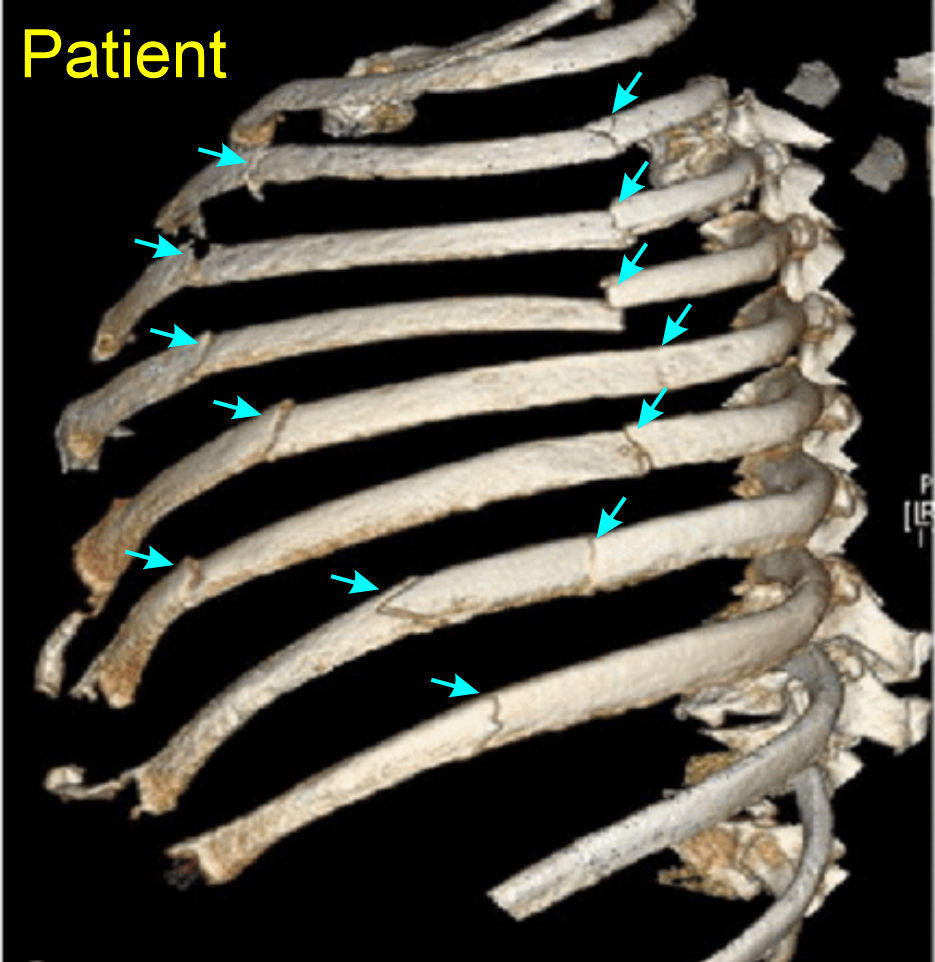

A patient was in a side car impact where the drivers side door collapsed inward impacting the anterolateral aspect of the patients left torso. The patient indicates they have extreme pain when moving their left arm and shortness of breath. The pain is significantly stronger than during quiet breathing. When moving the arm back and forth you hear a 'clicking' - Click here for sound - A chest film is ordered and shows